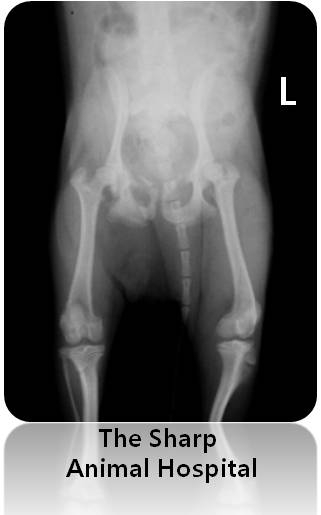

일단 걸음걸이가 이상하였기 때문에 뒷다리쪽과 골반쪽 엑스레이를 촬영하기로 하였습니다.

다리 쪽에서는 큰 문제가 보이지 않았어요.

그런데 정작 문제는 골반골에 있었습니다.

골반골에 골절이 있었어요..